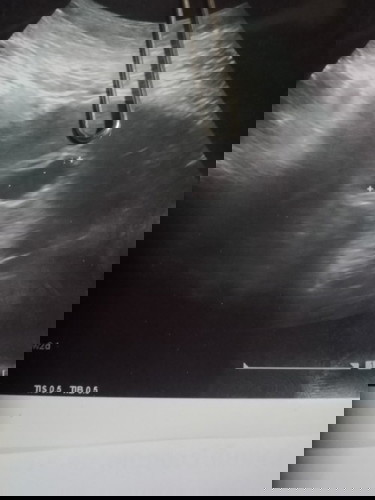

แม่ๆๆตรวจเจอน้องตอนกี่สัปดาห์คะ ตอนนี้ตั้งครรภ์ได้5w+5คะ อัลตราซาวด์แร้วเจอแต่ถุงการตั้งครรภ์ยังไม่เจอน้องเลยคะ หมอนัดอีก2อาทิ ถ้าไม่เจอหมอจะยุติการตั้งครรภ์คะแม่ ตอนนี้กังวลมากเลยคะ😣😣